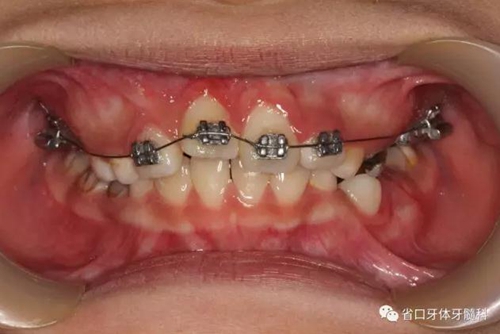

檢查:替牙列,12、21已萌出,11、22未萌,12、21間隙約5mm,右上前牙區(qū)前庭溝處見黏膜隆起,11牙冠未破齦。

口內(nèi)情況:正面觀

口內(nèi)情況:牙合 面觀